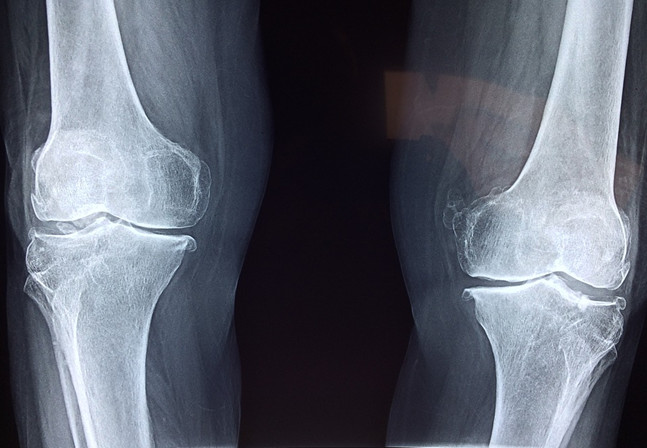

相反,如果身體當(dāng)中缺少氨糖補(bǔ)給的軟骨會(huì)怎么樣呢?在骨骼的摩擦中,原本飽滿健康的軟骨會(huì)被磨損,漸漸地保護(hù)骨骼的作用就會(huì)減弱,失去保護(hù)緩沖的動(dòng)作在完成肢體動(dòng)作時(shí)相互碰撞生痛,也就是許多中老年人遇到腿腳不便的情況了。

為什么是中老年人會(huì)遇到這樣的情況呢?事實(shí)上人體是能夠自身合成氨糖的,這保證了人體在幼年和青壯年時(shí)期的骨骼關(guān)節(jié)不會(huì)出現(xiàn)疼痛不便的現(xiàn)象,可隨著年紀(jì)增長(zhǎng),身體合成氨糖的速度和數(shù)量隨之減少了,也就開(kāi)始需要人自行從外界去補(bǔ)充氨糖才能保持關(guān)節(jié)的靈敏舒適。